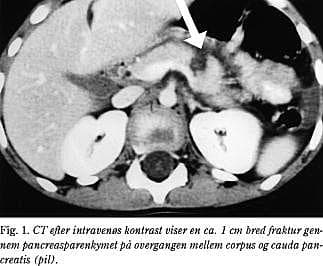

2. En 55-årig mand blev indlagt ca. 12 timer efter at være blevet sparket i abdomen. Patienten klagede ved indlæggelsen over tiltagende øvre abdominalsmerter. Objektivt fandtes han upåvirket og afebril. Blodtrykket blev målt til 150/60 mmHg og pulsen til 80. Abdomen fandtes blødt og med lokaliseret ømhed i epigastriet og ud under begge kurvaturer, men uden diffus peritonealia. S-amylase var på 542 U/l og leukocyttallet på 14,6 mia/l. Dynamisk CT (Fig. 2) viste et moderat ødem samt et tværgående hæmatom i corpus pancreatis. Den følgende dag var S-amylase steget til 2.228 U/l. En MR-scanning viste, at der var en læsion i corpus pancreatis, og ved MRCP (Fig. 3) blev der påvist diskontinuitet af ductus pancreaticus major. Ved laparotomi fandt man et hæmatom omkring milten samt en ruptur i pancreas ved collum pancreatis med overrevet ductus pancreaticus major. Der blev foretaget resektion af cauda og corpus pancreatis samt splenektomi. Det postoperative forløb var kompliceret af sekretion fra pancreasresektionsranden. Dette blev drænbehandlet med ophør af sekretion efter tre uger.

Dynamisk spiral-CT har en sensitivitet på 67-85% for læsioner i pancreas (12, 13). CT-diagnosen bygger dels på specifikke tegn: synlig pancreasfraktur, pancreashæmatom eller -forstørrelse, væske mellem vena lienalis og pancreas eller peripankreatisk hyperdensitet, og dels på uspecifkke tegn; fortykket Gerotas fascie, væske i lille sæk eller anden peritoneal væske, ekstraperitoneal væske eller andre organlæsioner (fx milten) i regionen. Selv alvorlige pancreaslæsioner med ductuslæsion kan dog være CT-negative i den akutte fase (14). CT'en viste i alle tre sygehistorier såvel specifikke som uspecifikke tegn, men kun i sygehistorie 1 og 2 fik patienten foretaget eksplorativ laparotomi på dette grundlag.